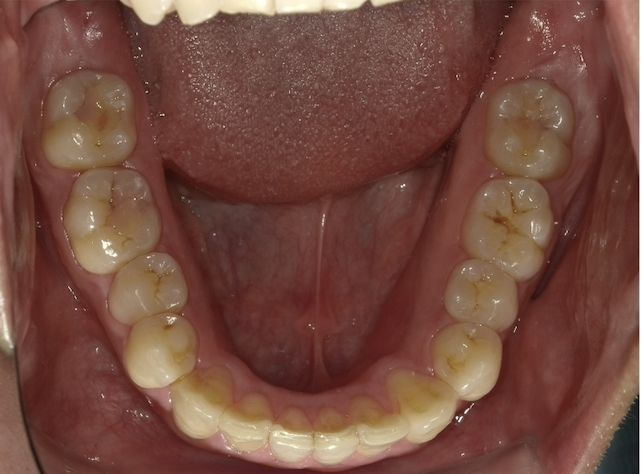

ガタガタ

Before

Before

Before

| 診断名 | 10代男性 ガタガタ |

|---|---|

| 費用 | 880,000円(税込) |

| 治療方法 | マウスピース矯正(インビザライン) |

| 治療期間 | 2年1ヶ月 |

| リスク・副作用 | ・治療の初期段階では、痛みや不快感が生じやすくなりますが、1週間前後で慣れます。 ・歯の動き方には個人差があるため、予想された治療期間より延長する場合があります。 |